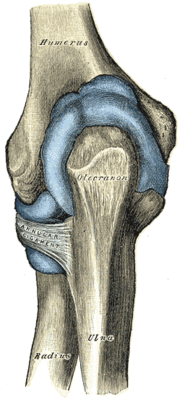

![]() Left elbow-joint, showing anterior and ulnar collateral ligaments. | |

المرفق إنگليزية: Elbow هي عظمة مفصلية تربط عظمة العضد مع عظمتي الزند و الكعبرة. وتكون أماكن الالتقاء الثلاثة، ثلاثة مفاصل أصغر وتسمح هذه المفاصل الصغيرة بحركات معينة، حيث يسمح مفصلا العضد ـ الزند والعضد ـ الكعبرة للشخص بثني الساعد إلى أعلى وأسفل، بينما يسمح مفصلا الكعبرة ـ الزند والعضد ـ الكعبرة بدوران الساعد وكذلك راحة اليد أعلى وأسفل.

يحيط بمفصل الكوع كبسولة من نسيج متين. وتقوم هذه الكبسولة مع عدد من الأنسجة القوية الحبلية الشكل التي تُعرف بالأربطة بالمحافظة على العظام في أماكنها. ويعمل السائل الزيلي بمثابة مزلق لتقليل الاحتكاك عند الكوع.

أجزاء مشتركة

| Joint | From | To | Description |

| humeroulnar joint | trochlear notch of the ulna | trochlea of humerus | Is a simple hinge-joint, and allows of movements of flexion and extension only. |

| humeroradial joint | head of the radius | capitulum of the humerus | Is a hinge-joint joint. |

| proximal radioulnar joint | head of the radius | radial notch of the ulna | In any position of flexion or extension, the radius, carrying the hand with it, can be rotated in it. This movement includes pronation and supination. |